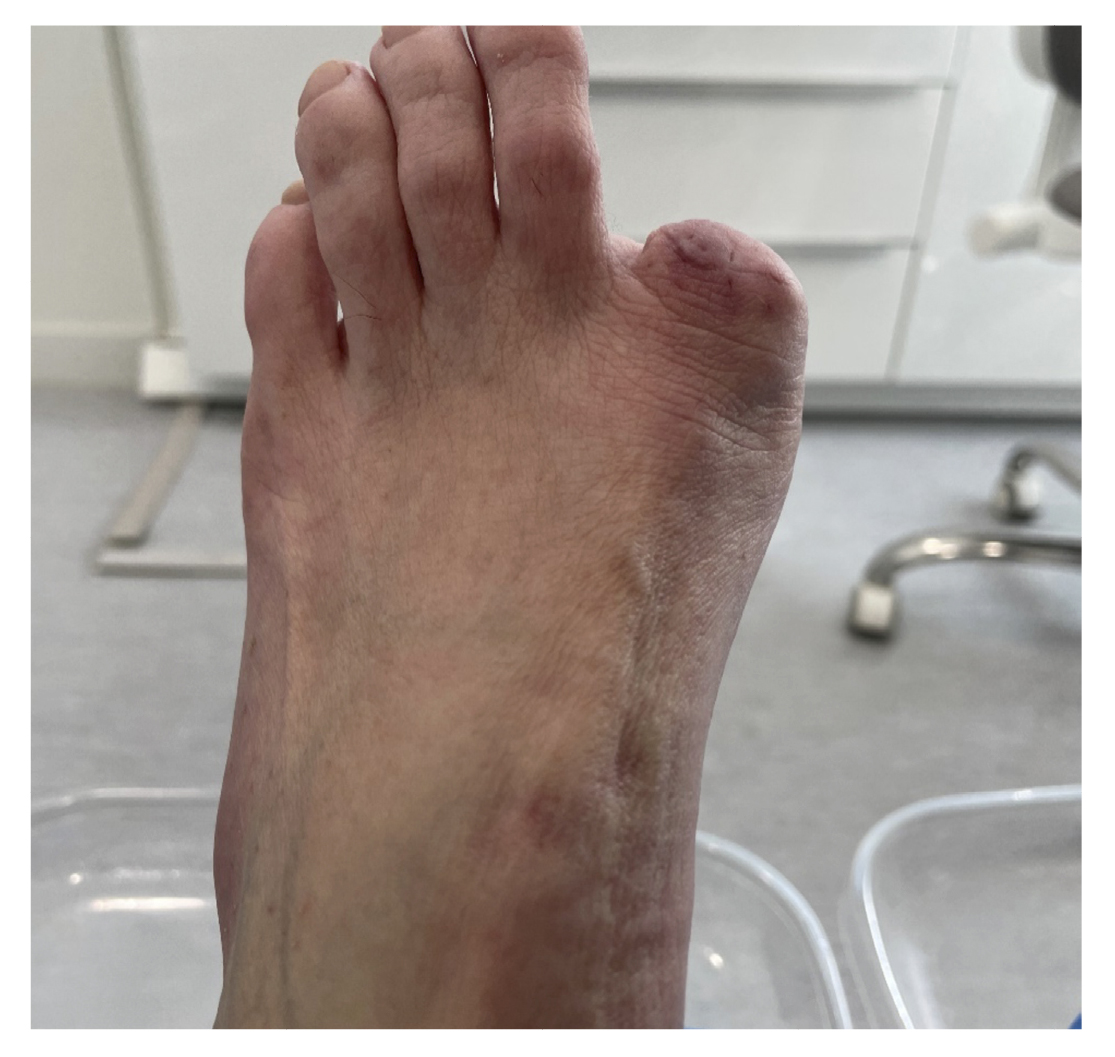

The patient reported a 7-month history onychocryptosis (September 2022) on the medial border of the first toe of the left foot, with presence of ungual granulation tissue on said border, causing her pain and digital inflammation (Figure 1). The patient received treatment from her podiatrist consisting of chiropody and canal cleaning, and then daily dressings with mupirocin were prescribed for the lesion. The lesion showed poor progression in the following days with increased pain and tenderness to the touch. Treatment was modified to amoxicilin/clavulanic acid 875/125 mg, 1/8 hours along with the use of oral analgesics (Figure 2). The patient continued with poor symptomatic evolution and attended her health center where an X-ray was performed, ruling out the presence of deep infection (osteomyelitis).

Figure 1. Initial process of onicochryptosis and reactive granuloma.